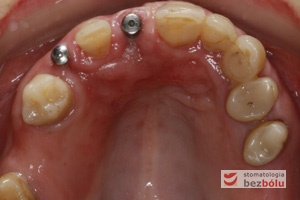

Implanty in situ - widok okluzyjny wprowadzonych wszczepów 1 mm podwyrostkowo

Implanty in situ – widok okluzyjny wprowadzonych wszczepów 1 mm podwyrostkowo